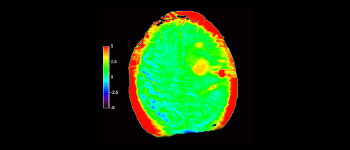

In a society where neurological disorders represent a heavy burden, Philips is committed to provide superb diagnostic clarity and treatment guidance for all patients. Today, although MR is the gold standard in neuro oncology imaging, its accuracy in tumor grading and treatment follow up assessment can be further improved. 3D APT (Amide Proton Transfer) is a unique, contrast-free, brain MR imaging method addressing the need for more confident diagnosis in neuro oncology. 3D APT uses the presence of endogenous cellular proteins, to produce an MR signal that directly correlates with cell proliferation, a marker of tumoral activity. 3D APT can support trained medical professionals in differentiating low grade from high grade gliomas and, in differentiating tumor progression from treatment effect1.

APT was added to about 70 MRI exams of children with brain tumor and we saw some encouraging early results”